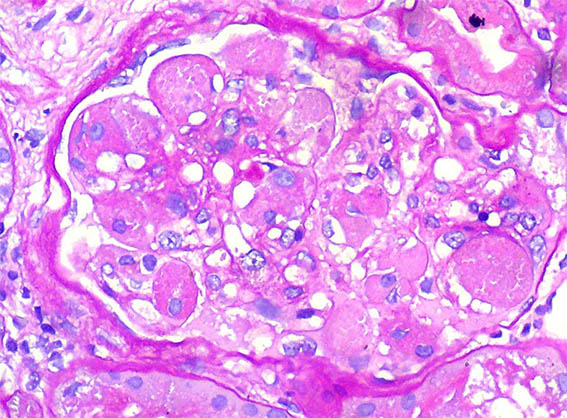

Se hace biopsia renal, observe las imágenes.

Figura 3.

PAS, X400.